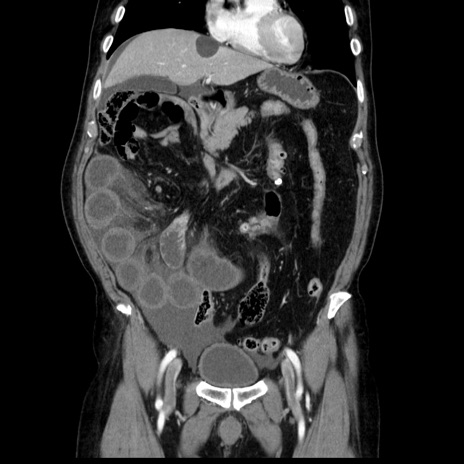

症例30(冠状断像)

【症例】80歳代男性

【主訴】臍周囲痛

【現病歴】約6時間前から臍下部痛が出現。次第に腹部膨隆・背部痛も生じてきたため来院。背部痛の場所は変化しない。

【身体所見】意識清明、BT 36.3℃、BP  131/87mmHg、P 87bpm、SpO2 100%(RA)、臍周囲自発痛・圧痛あり、反跳痛なし、自発痛部位に一致して板状硬あり、腹部膨隆、腸雑音減弱、CVA tenderness両側陰性。

【データ】WBC 19600、CRP 0.33